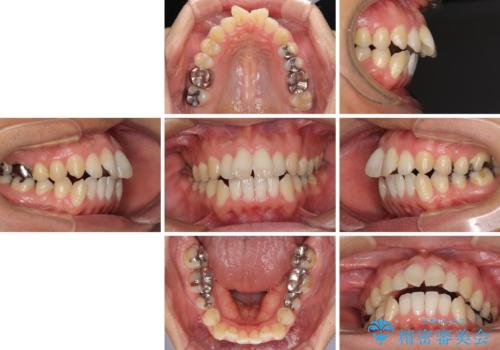

- 前歯のデコボコと、上顎前歯の突出感を気にして来院された患者様です。

通常の咬み合わせ位置と比較して、上顎の歯列が全体的に前方にある状態で、上下前歯の前後方向の位置に著しい差がありました。

上顎奥歯付近にアンカースクリューを用い、上顎歯列全体の後方移動と、大臼歯圧下を促し、前歯の上下関係を改善することとしました。

奥歯には目立つ銀歯が多くあるので、矯正治療後には下顎の銀歯をセラミッククラウンやセラミックインレーにより、補綴・修復治療することとしました。